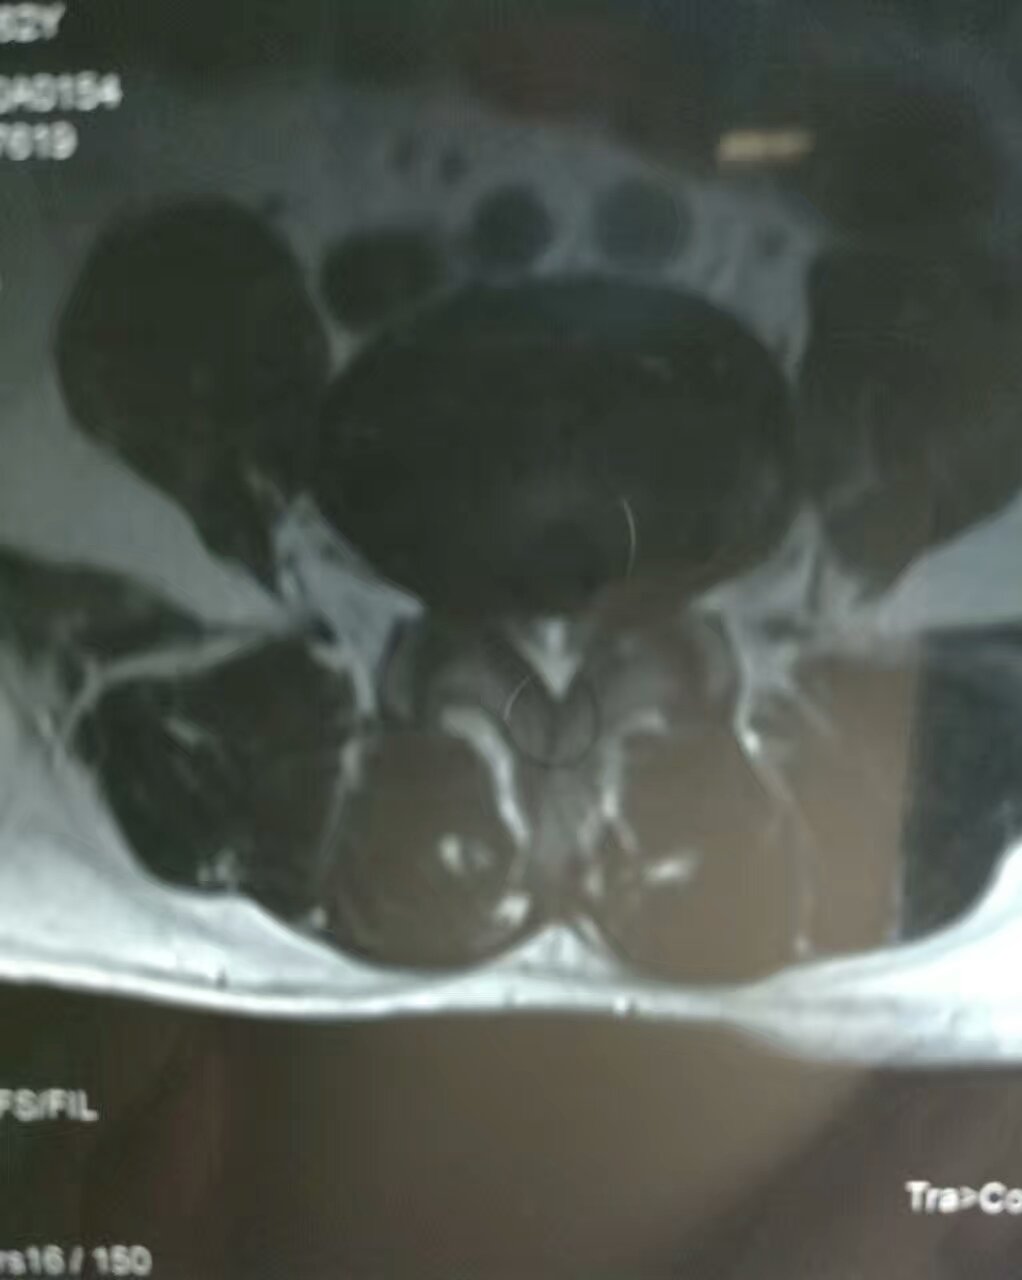

陈某,男,62岁,弧刃射频针治疗腰4、5椎间盘突出症。

赵某,男,47岁,17年前曾行开放性手术后好转,后间断反复慢性腰痛,两月前再次复发加重,间歇性跛行,影像学等检查,考虑腰5骶1椎间盘突出症,顺利弧刃射频针联合臭氧微创髓核消融治疗。